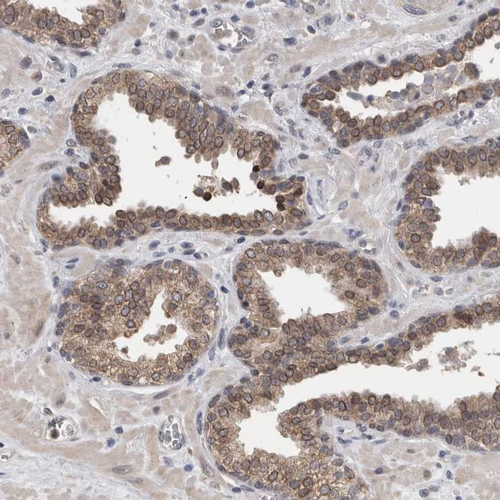

Immunohistochemical staining of human heart muscle shows moderate cytoplasmic positivity in cardiomyocytes.